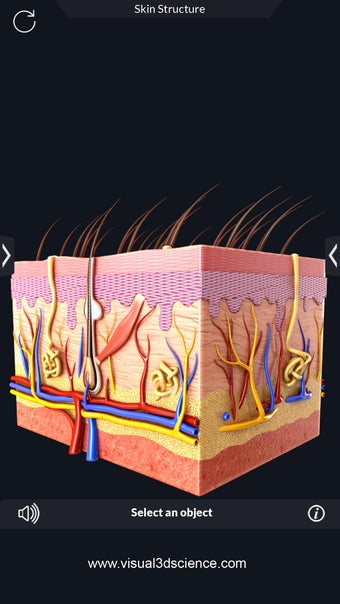

La anatomía humana es una aplicación educativa médica que te permite explorar el cuerpo humano desde todos los ángulos. Ofrece una mirada detallada a la anatomía de los diferentes sistemas, así como a los órganos y sus funciones. Es una referencia perfecta para estudiantes y profesores de medicina.

Puedes seleccionar cada parte del cuerpo por separado para ver su nombre o leer información relacionada. Puedes ocultar y mostrar cada parte del cuerpo, así como rotar 360° alrededor de un modelo 3D altamente realista. Puedes dibujar en la pantalla o compartir capturas de pantalla con tus amigos. Puedes encontrar la definición de cada parte del cuerpo y su anatomía.